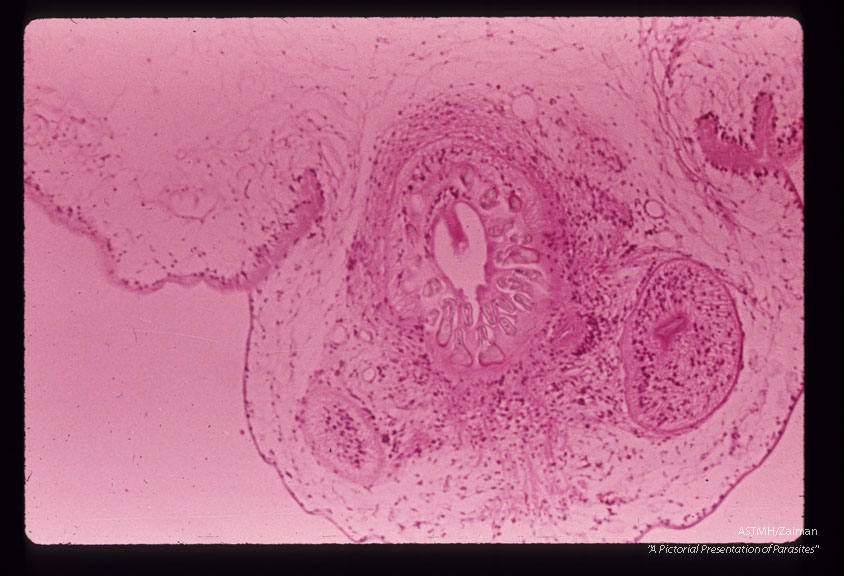

A 32 month old white male in South Dakota suffered progressive lassitude,   anorexia,   irritability,   incoordination and infrequent vomiting.  A suboccipital craniotomy was performed during which a grape-like mass of translucent thin wall cysts was discovered and partially evacuated with difficulty.  Subsequently patient developed flexion rigidity of the  extremities,  non-reactive pupils and decreased consciousness.  A sinus tract at the operative site con­tained more cysts.  The patient died three months after the onset of symptoms.  Section through scolex and membrane.

Multiceps

Description: A 32 month old white male in South Dakota suffered progressive lassitude, anorexia, irritability, incoordination and infrequent vomiting. A suboccipital craniotomy was performed during which a grape-like mass of translucent thin wall cysts was discovered and partially evacuated with difficulty. Subsequently patient developed flexion rigidity of the extremities, non-reactive pupils and decreased consciousness. A sinus tract at the operative site con­tained more cysts. The patient died three months after the onset of symptoms. Section through scolex and membrane.